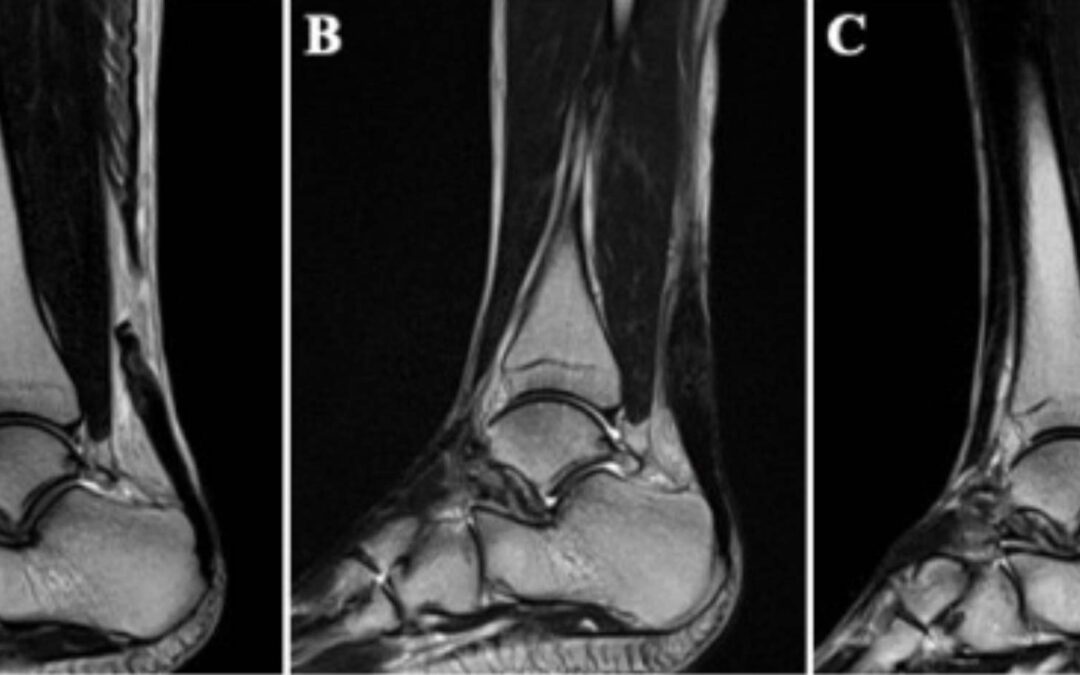

Figure. MRI evaluation detected high signal intensity of the sutured tendon in 25% (2 of 8 patients) at 12 weeks postoperatively and in 0% (0 of 8 patients) at 24 weeks postoperatively. MRI of case 2. Preoperative MRI revealed that the Achilles tendon was ruptured in the mid-substance of the tendon (A). The high signal intensity at the repaired site of the Achilles tendon revealed by MRI taken 12 weeks postoperatively (B) had improved by 24 weeks postoperatively (C).

The 8 patients consisted of 7 male and 1 female athletes with a mean age of 28.5 ± 5.2 years (range, 23-39 years) at the time of surgery. All patients were high-level athletes with a mean Tegner activity score of 9.0 ± 0.5 (range, 8-10). The mean AOFAS score improved significantly from 36.0 ± 9.4 preoperatively to 96.8 ± 3.6 at 1 year postoperatively (P< 0.001). The mean time to be able to perform 20 continuous DHR and 20 continuous SHR was 6.8 ± 0.8 weeks and 10.1 ± 1.6 weeks, respectively. All patients could return to their original sport at preinjury levels with the mean time of 18.3 ± 2.7 weeks. Also, there were no complications related to surgery or injection. Furthermore, T2-weighted MRI showed the high signal intensity of the sutured tendon in 25% (2 of 8 patients) at 12 weeks and 0% (0 of 8 patients) at 24 weeks postoperatively.